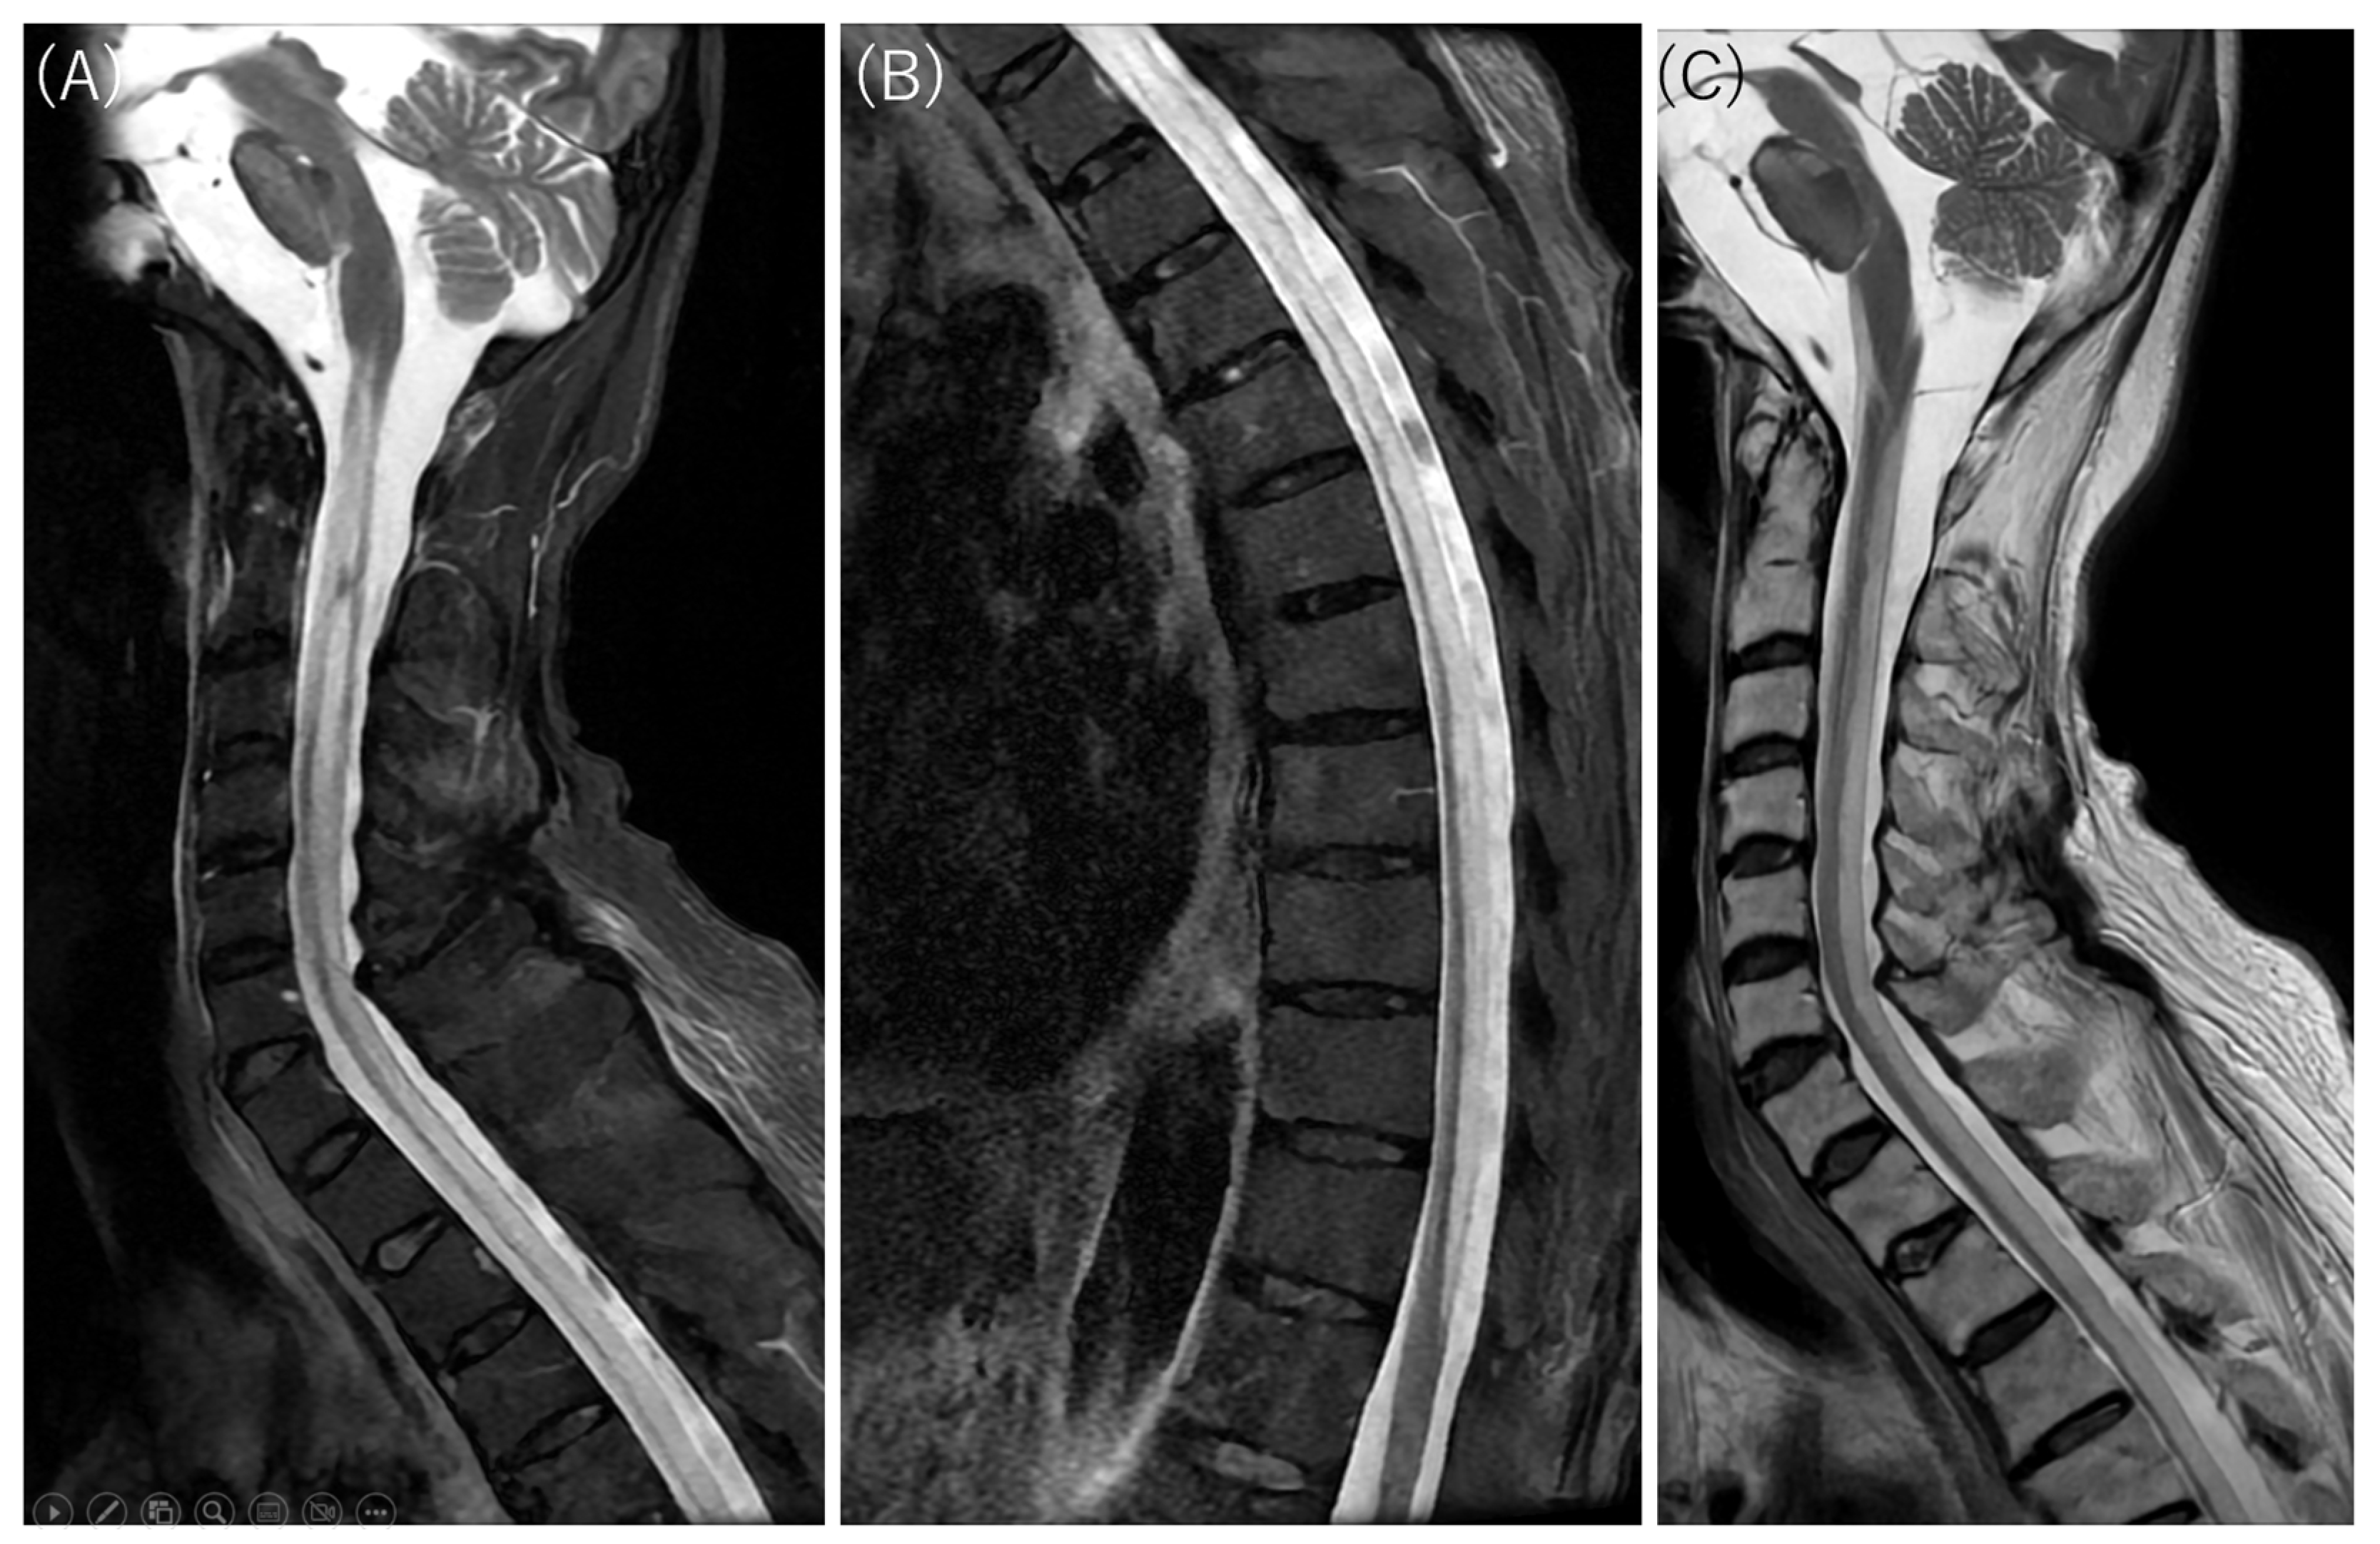

Cervicothoracic MRI on DWI, diffusion-weighted whole-body imaging with background body signal (DWIBS), and ADC map results. (A) DWI demonstrates longitudinal hyperintensity extending from the cervical to the lumbar spinal cord (arrows). Similarly to the intracranial findings, this lesion demonstrated restricted diffusion. (B) DWIBS vividly displays high signal intensity along the entire cervicothoracolumbar spinal cord (arrows). DWIBS, first described by Takahara et al. in 2004 [1,2], is a sophisticated MRI technique rooted in DWI, which probes tissue microstructure via water molecule Brownian motion [2,3]. Employing short tau inversion recovery (STIR) echo-planar imaging (EPI) [1,2,3], it applies fat suppression and intense diffusion weighting to mute signals from healthy tissues, generating a stark “black background” [2,3]. Regions of restricted diffusion—e.g., malignancies, abscesses, or acute inflammation—stand out as bright hyperintensities [1,2,3,4,5]. These can be rendered as 3D PET-like images and co-registered with T2-weighted sequences for superior anatomical correlation [2,3]. (C) ADC maps show low ADC values corresponding to the areas of high signal intensity on DWI (arrows).